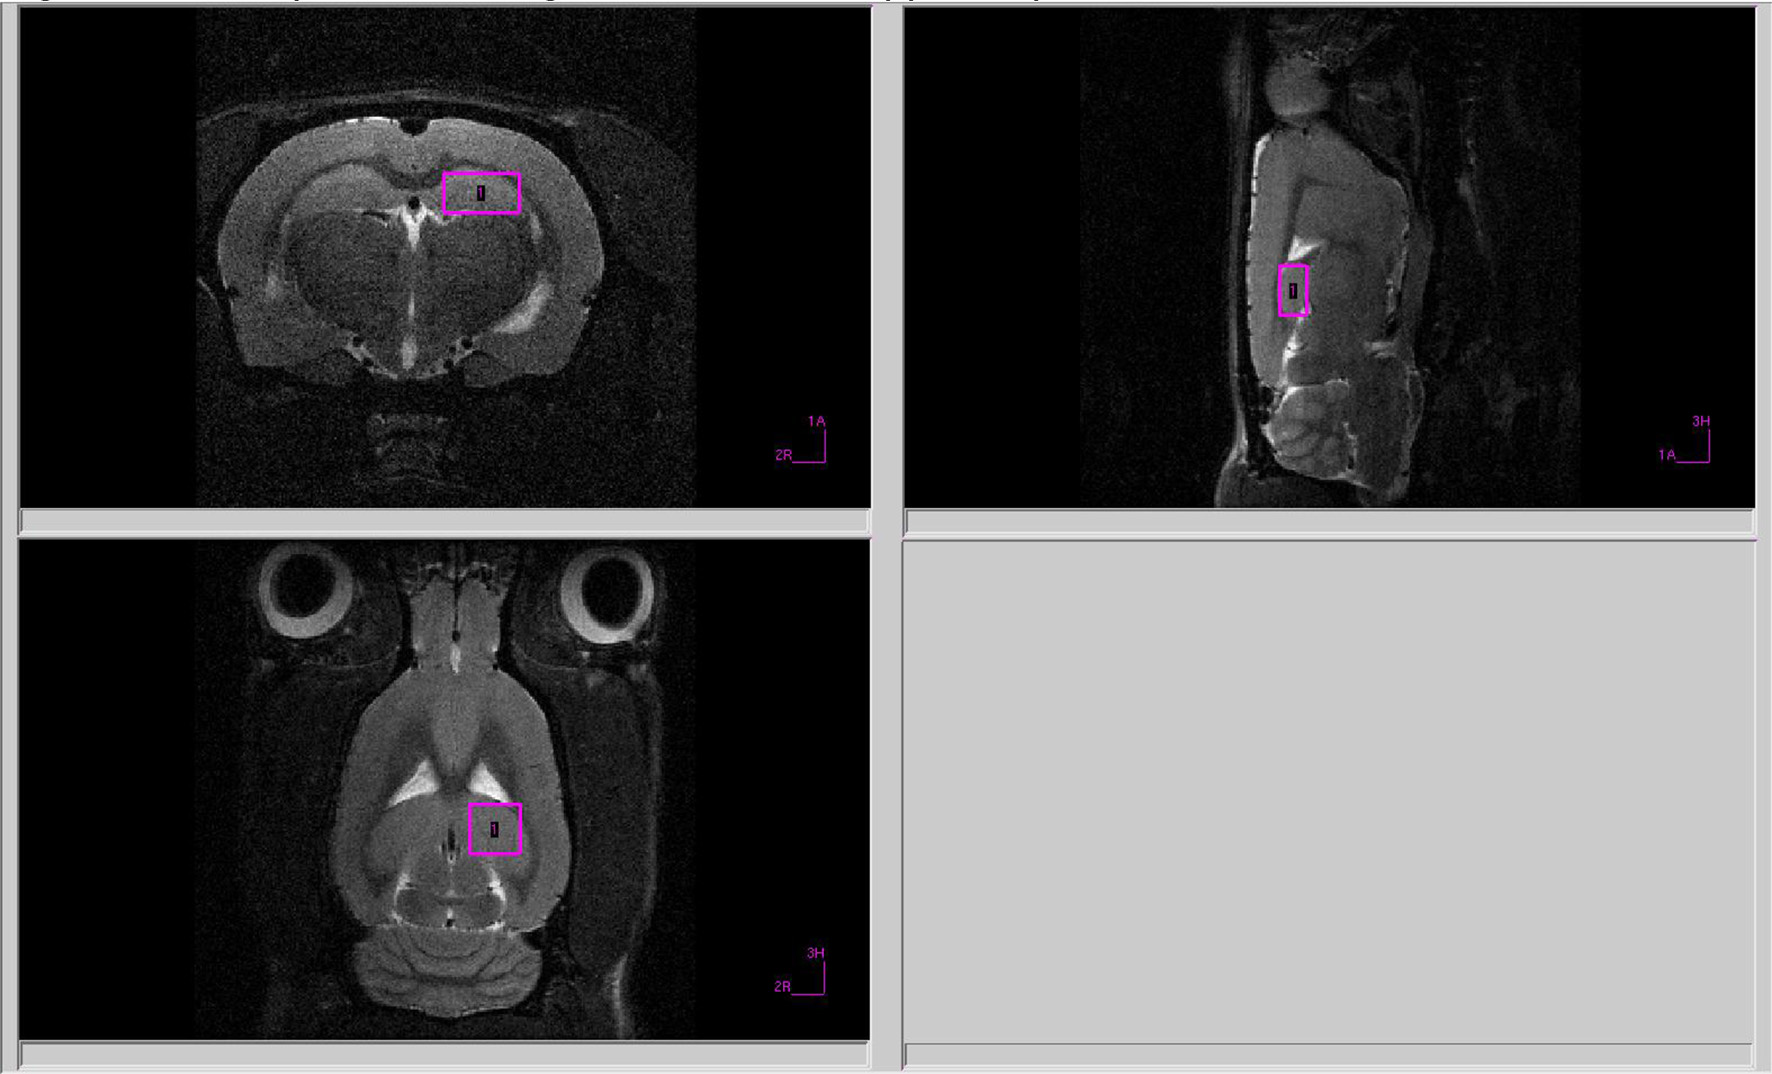

Magnetic Resonance Spectroscopy (MRS)

Rat amygdala and hippocampal neurometabolites were measured on a horizontal tomograph with a magnetic field of 11.7 Tesla (Bruker, Biospec 117/16 USR, Germany). The rats were anesthetized with gas (Isoflurane; Baxter Healthcare Corp., Deerfield, IL) using a Univentor 400 Anesthesia Unit (Univentor, Zejtun, Malta). The tomograph table contained a water circuit that maintained a surface temperature of 30°C, to preserve animal body temperature during the test. A pneumatic respiration sensor (SA Instruments, Stony Brook, NY), placed under the lower body, controlled the depth of anesthesia.

All proton spectra of the rat amygdala and hippocampus were recorded with transmitter volume (T11232V3) and rat brain receiver surface (T11425V3) 1H radiofrequency coils (Bruker, Ettlingen, Germany). High-resolution T2-weighted images of the rat brain in three (axial, sagittal, and coronal) dimensions (section thickness, 0.5 mm; field of view, 2.5 × 2.5 cm for axial and 3.0 × 3.0 cm for sagittal and coronal sections respectively; matrix of 256 × 256 dots) were recorded by rapid acquisition with relaxation enhancement (TurboRARE), with the pulse sequence parameters TE = 11 ms, TR = 2.5 s for correct positioning of the spectroscopic voxels. Voxel dimensions were 3.0 × 1.5 × 3.0 mm for amygdala and 1.5 × 3.0 × 3.0 mm for the hippocampus. All voxels were manually placed according to a structural T2-weighted MRI images (Figures 1, 2). All proton spectra were recorded by spatially localized single-voxel stimulated echo acquisition mode (STEAM) spectroscopy with the pulse sequence parameters TE = 3 ms, TR = 5 s, 120 accumulations. Uniformity of the magnetic field was tuned within the selected voxel using FastMap (Gruetter, 1993) before each spectroscopic recording. The water signal was inhibited with a variable pulse power and optimized relaxation delays (VAPOR) sequence (Tkac et al., 1999).